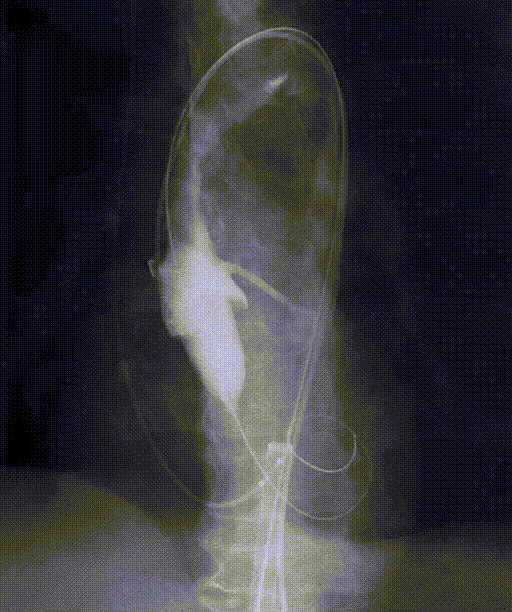

腹主动脉、双侧髂总及双侧股动脉显影情况,股动脉细小(左)。

髂总动脉入路:缝合荷包-荷包穿刺造影(右)。

经左髂总动脉入路置入20F亲水涂层鞘,过程顺利。